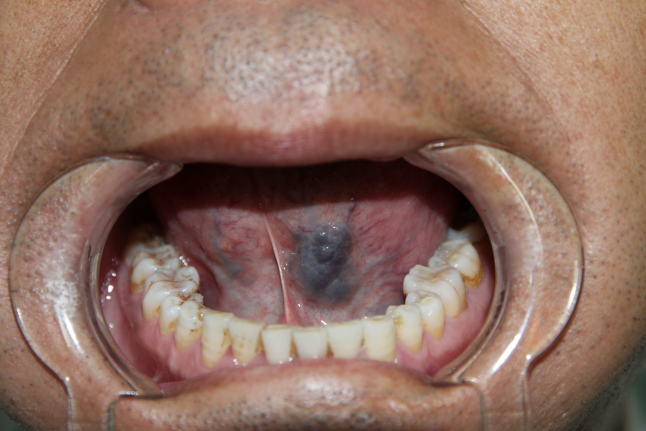

骨髓移植口腔排异图片

图一图一是一位5年前做了骨髓移植的患者,反复出现口腔和皮肤排异

术前口腔像

聚桂醇注射治疗口腔血管畸形

不做骨髓移植没有命,做了骨髓移植后的排异反应也可能随时要了启铭的